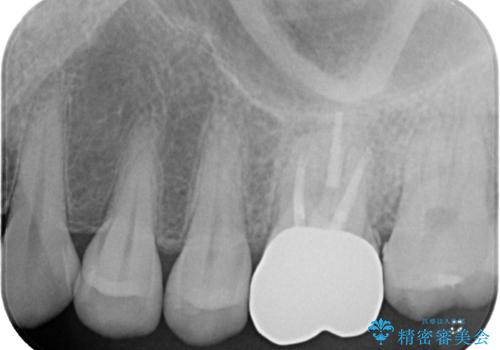

- 奥歯で咬んだときに痛みがあり、膿の出口が現れたとのことで来院された患者様です。

かかりつけ医では治療が困難と言われたとのことで当院にいらっしゃいました。

診査を行った結果、まずは根管治療を行うこととしました。

咬み合わせが非常に強く、臼歯のみに咬合力が集中している咬み合わせだったので、根管治療後はPGAクラウン(白金加金合金クラウン)にて補綴する治療計画となりました。